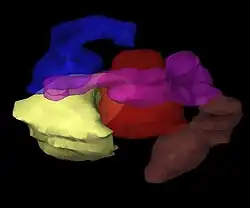

Création d'un patient virtuel

Les images du patient portant les applicateurs in situ sont importées dans un logiciel de planification du traitement. Le patient est alors amené dans une salle spéciale et blindée pour le traitement. Le logiciel de planification du traitement permet l'acquisition de multiples images 2D du site de traitement. Ces images sont traduites en un « patient virtuel » 3D, dans lequel la position des applicateurs peuvent être définis. Les relations spatiales entre les applicateurs, le site de traitement et les tissus environnants sains sont dans ce « patient virtuel », une copie des relations dans le patient réel.

Optimisation du plan d'irradiation

Pour identifier la optimale répartition spatiale et temporelle des sources de rayonnement dans les applicateurs sur ses cibles, le logiciel de planification du traitement place dans un premier temps les sources de rayonnement virtuelles à l'intérieur du patient virtuel. Le logiciel montre une représentation graphique de la distribution de l'irradiation. Cette étape sert de guide à l'équipe de curiethérapie pour affiner la répartition des sources et de fournir un plan de traitement qui est parfaitement adaptée à l'anatomie de chaque patient. Ensuite, la radiation du patient réel peut commencer. Cette approche est parfois appelée « peinture de la dose ».